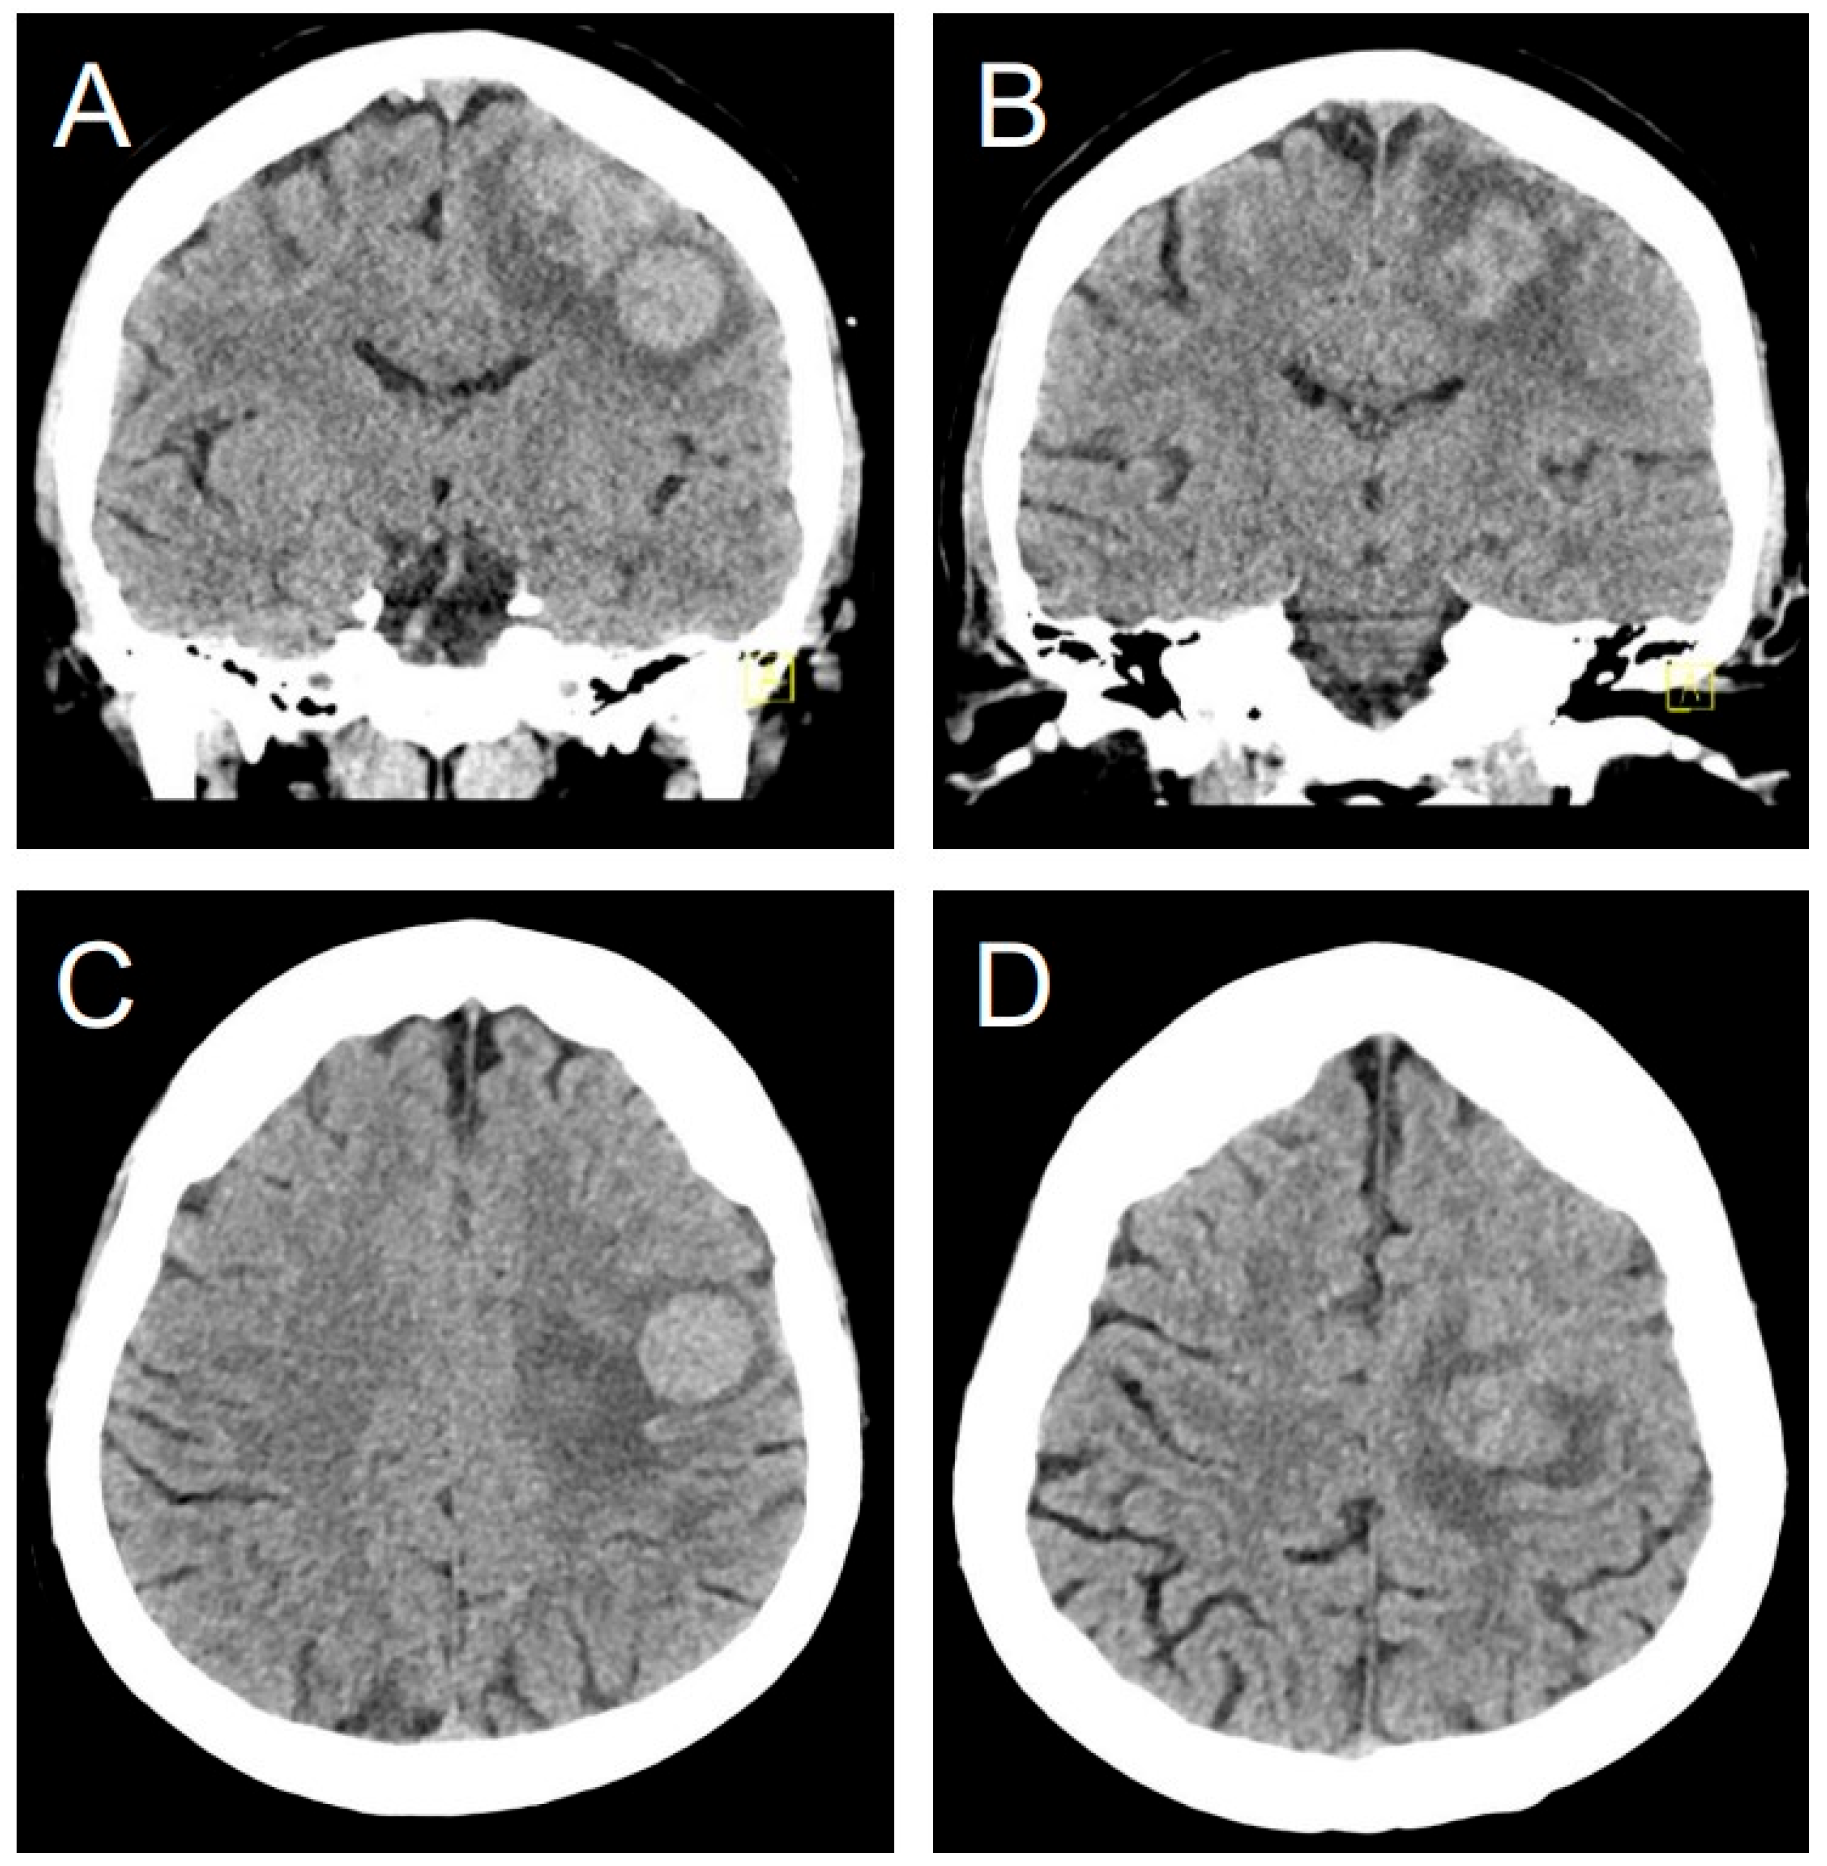

3.8. Illustrative Case